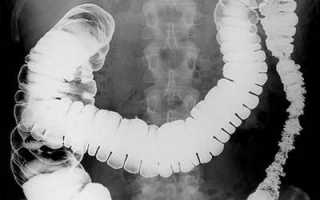

Рентген пищевода и желудка проводят с применением бариевого контраста, который наполняет не только пищевод и желудок, но и кишечник. Таким образом, при одном обследовании можно посмотреть состояние всего пищеварительного тракта. Барий напоминает кашицеобразную массу, консистенции сметаны, белого цвета, на вкус как мел.

Рентгенологическое обследование пищевода и желудка – это оптимальная, легко переносимая пациентом процедура. Она используется даже у тяжелобольных пациентов, когда проведение эндоскопии затруднительно. При рентгеноскопии отлично просматриваются все сегменты пищеварительного тракта, отделы желудка, можно исследовать двенадцатиперстную кишку, тонкий и толстый кишечник.

Для подробного исследования слизистой используется метод двойного контрастирования с помощью бария и воздуха. Бариевые массы задерживаются между складками органов пищеварения. Газ создает просветление на рентгеновском снимке, на фоне которого отчетливо вырисовывается рельеф слизистой.